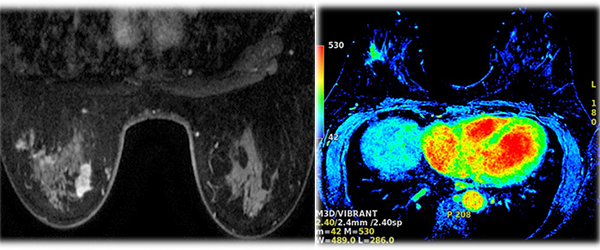

Breast MRI

Breast MRI (magnetic resonance imaging) uses radio waves and strong magnets to make detailed pictures of the inside of the breast, and primarily used as a supplemental tool to breast screening with mammography or ultrasound. It may be used to screen women at high risk for breast cancer, evaluate the extent of cancer following diagnosis, or further evaluate abnormalities seen on mammography. Breast MRI does not use ionizing radiation, and it is the best method for determining whether silicone breast implants have ruptured.